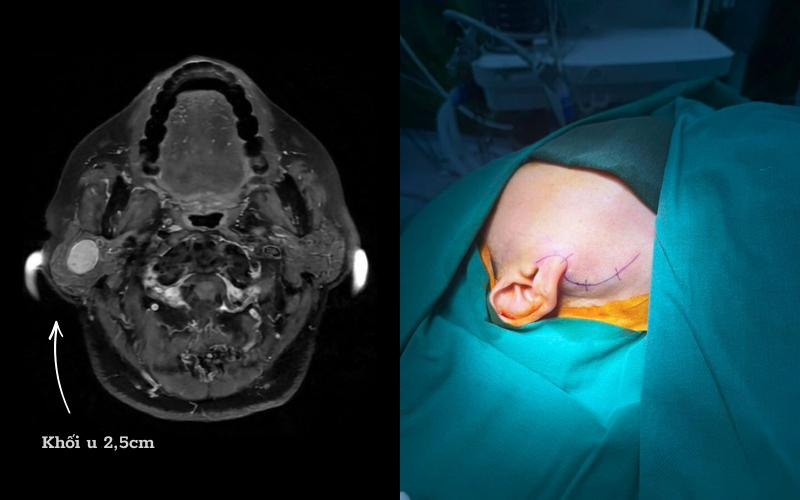

Trường hợp bệnh nhân D. là ví dụ điển hình, người bệnh phát hiện khối u tuyến mang tai phải từ nhiều năm trước, có biểu hiện sưng lệch vùng góc hàm, thỉnh thoảng đau tức. Dù đã được chỉ định phẫu thuật từ sớm nhưng bệnh nhân liên tục trì hoãn do lo ngại có nguy cơ liệt mặt sau mổ.

Nhờ đó, với những khối u có kích thước phù hợp (nhỏ hơn 3cm), bác sĩ có thể “đi đường tắt” bằng kỹ thuật extra-capsular: tiếp cận trực tiếp khối u và bóc tách ngay trên bao u thay vì phải bộc lộ toàn bộ dây thần kinh. Cách làm này giúp giảm tối đa nguy cơ tổn thương dây thần kinh số VII, đồng thời bảo tồn phần lớn nhu mô tuyến mang tai lành, giữ được hình dạng tự nhiên vùng mang tai sau mổ.

Ca phẫu thuật của bệnh nhân D. kéo dài khoảng 3 giờ, kết quả thành công tốt đẹp. Khối u được lấy trọn vẹn mà không cần cắt bỏ toàn bộ tuyến mang tai. Sau mổ, người bệnh D. hồi phục tốt, không ghi nhận liệt dây thần kinh mặt. Đặc biệt, gương mặt cân đối, không méo lệch, chức năng vận động và yếu tố thẩm mỹ được bảo tồn nguyên vẹn.